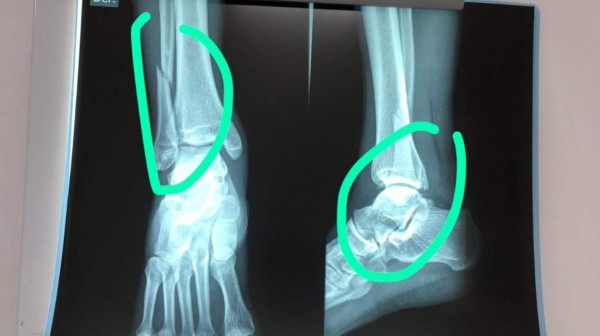

“Erick Andino doble quebradura, y creen que el árbitro solo pitó en contra, dejen de especular el árbitro pitó mal porque es malo, están son las consecuencias de no tener autoridad en la cancha”, informó Eddy Atala y adjunto esta imagen de la lesión.